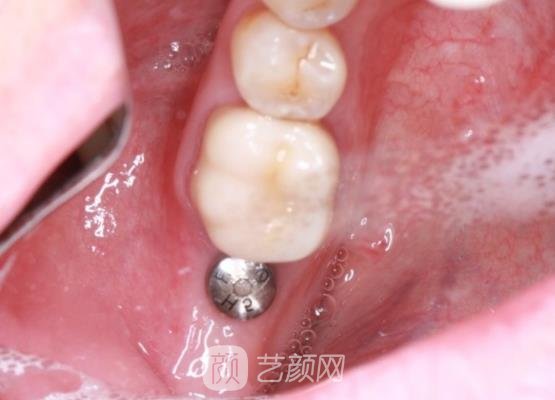

果然和网上说的一样,选择这样的医院医生,真的让我感到很欣慰,我和医生说明了我的自身情况,医生根据我的牙齿情况为我推荐了合适的手术方案。并且还对我讲解了关于手术的操作流程以及原理,等我了解了之后,医生就决定为我做手术,在操作过程当中进行的很顺利。

手术当中由于麻醉的缘故,我也没有感觉到疼痛,进行的很不错,大概持续了2~3个小时左右就已经完成了。术后医生还仔细的交代了一些相关的护理知识,我听了医生的讲解之后,便回到家里做了休养的工作,在休养的阶段,我一直对于口腔做了保护,没有吃那些过于坚硬的食物。

现在距离手术已经过去三个多月了,牙齿情况恢复得很不错,真的令我感到很满意。自从做了手术之后,我感觉时间过得还是蛮快的,现在已经过去半年多了,牙齿状态恢复好了,变得很自然。